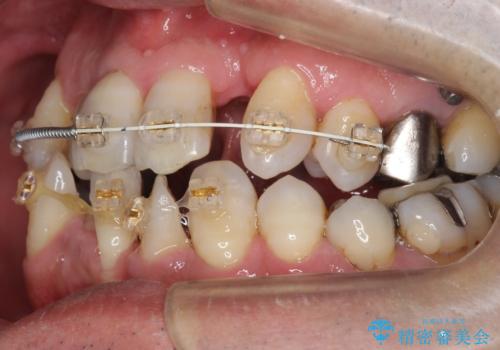

前歯の部分矯正を行い受け口を改善しました。

奥歯まで動かそうとすると顎の手術の適応になってしまうため、奥歯はそのままにして前歯のかみ合わせを改善しました。

また、奥歯はインプラント治療を行い、矯正で下の前歯を後ろに下げるのに使用しています。

時間はかかりましたがしっかり治療することができました。